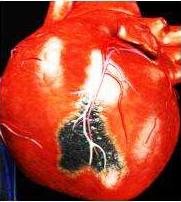

冠心病是指供应心脏本身的冠状动脉血管发生动脉粥样硬化病变而引起血管腔狭窄或阻塞,造成心肌缺血、缺氧、坏死而导致的一类心脏病,常常简称为"冠心病"。

我们知道供应心脏的血管有3根,分别是左前降支,左回旋支,右冠状动脉。因为这3根血管像一顶皇冠一样覆盖心脏上面,所以叫冠状动脉。